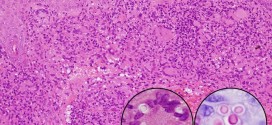

La balonización. Termino para el proceso cutáneo. Hinchazón cutánea de las células malpigianas en que sus núcleos se multiplican y forman verdaderos balones que acaban por estallar. Estructuras más o menos esféricas; se observa en algunas infecciones provocadas por herpes zona, como en la varicela. Información: Para más información sobre esta enfermedad o patología, si usted cree que es necesario, …